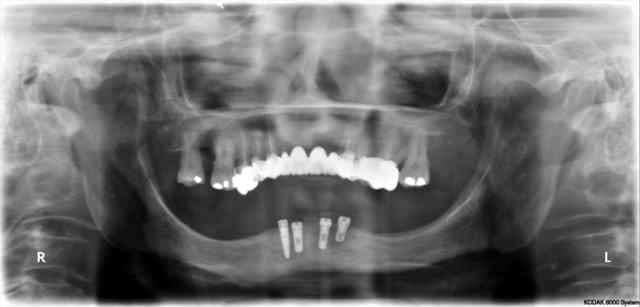

pano 5 et photo 6 ce matin